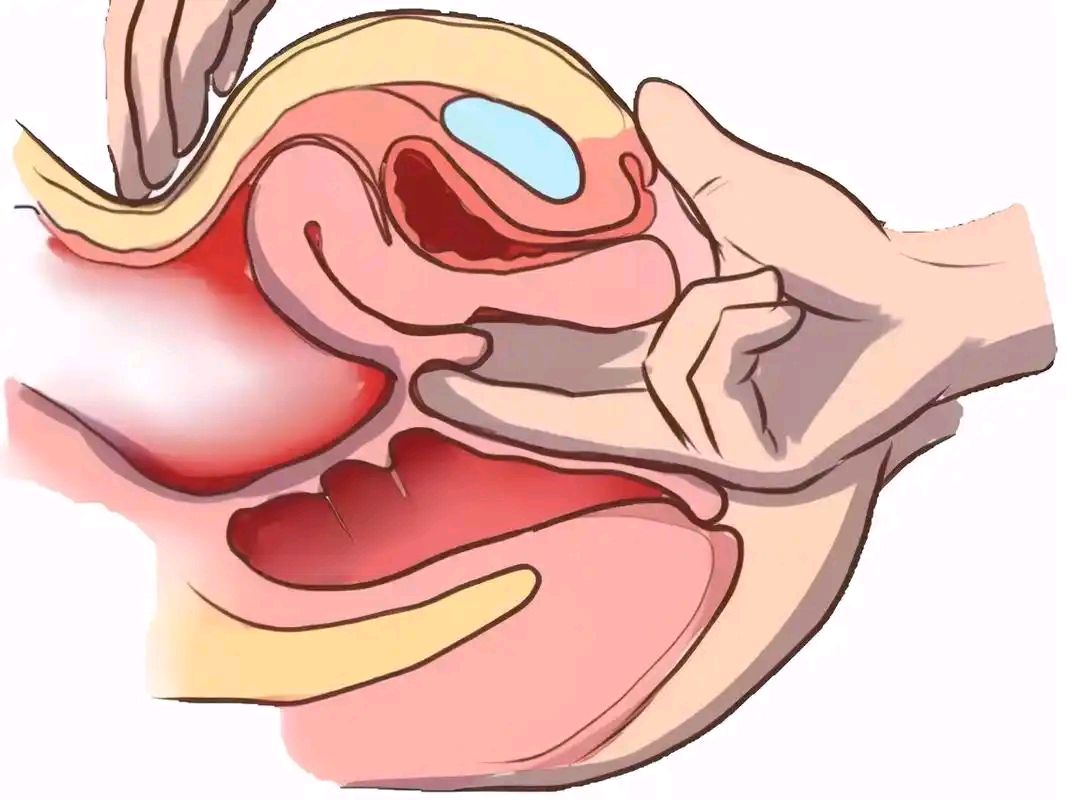

方法:患者仰卧位或站立位(便于模拟盆底受力时的解剖学变化),医生双手戴手套,润滑后进行检查。将手指置入患者的阴道内,轻轻触诊阴道后壁。让患者进行Valsalva动作(即用力屏气,模拟排便动作)。观察并感知阴道后壁是否有异常膨出,并记录膨出的大小、柔软程度及是否伴有压痛。

作用:1.筛查直肠前突(Rectocele)及其他盆底结构功能异常等出口梗阻型便秘。2.排查其他盆底异常(如阴道壁脱垂、膀胱膨出、子宫下垂等),因为这些问题可能与直肠前突同时存在,影响综合治疗方案的制定。

适应症:

1.排便时需要按压阴道后壁协助排便的患者。如果阴道后壁的膨出物体积较大且柔软,且患者报告需要用手压迫阴道来辅助排便,提示该直肠前突可能是便秘的主要原因。

2.有明确排便困难、不尽感,并伴有下腹坠胀或阴道异物感。

3.怀疑存在盆底结构松弛或脱垂(如直肠前突、阴道后壁膨出等)的患者。